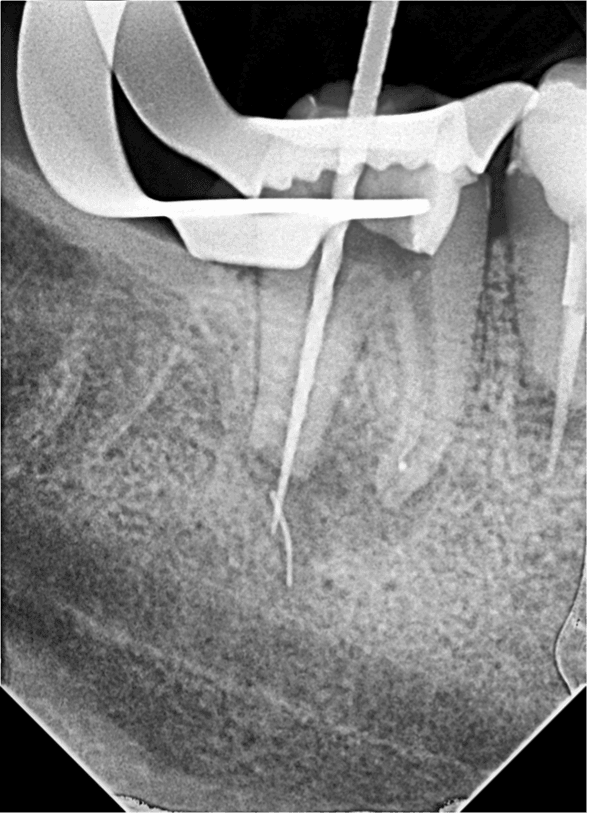

Kırık eğenin etrafından ultrasonik uç ile preparasyon yapılmaya çalışıldı ancak eğenin apikalde duvarla teması olmadığı ve tamamen granülasyon dokusu içerisinde olduğu anlaşıldı (RESİM 3).

Resim 3: Kırık eğenin granülasyon dokusu içerinde kayboluşu